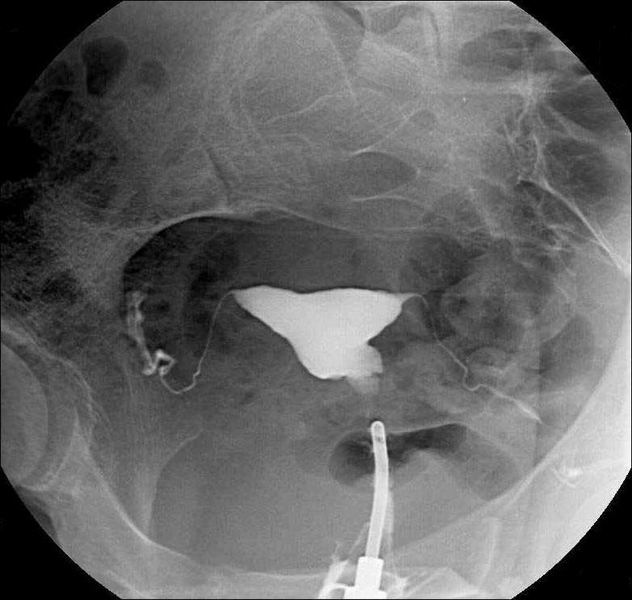

Cystografie